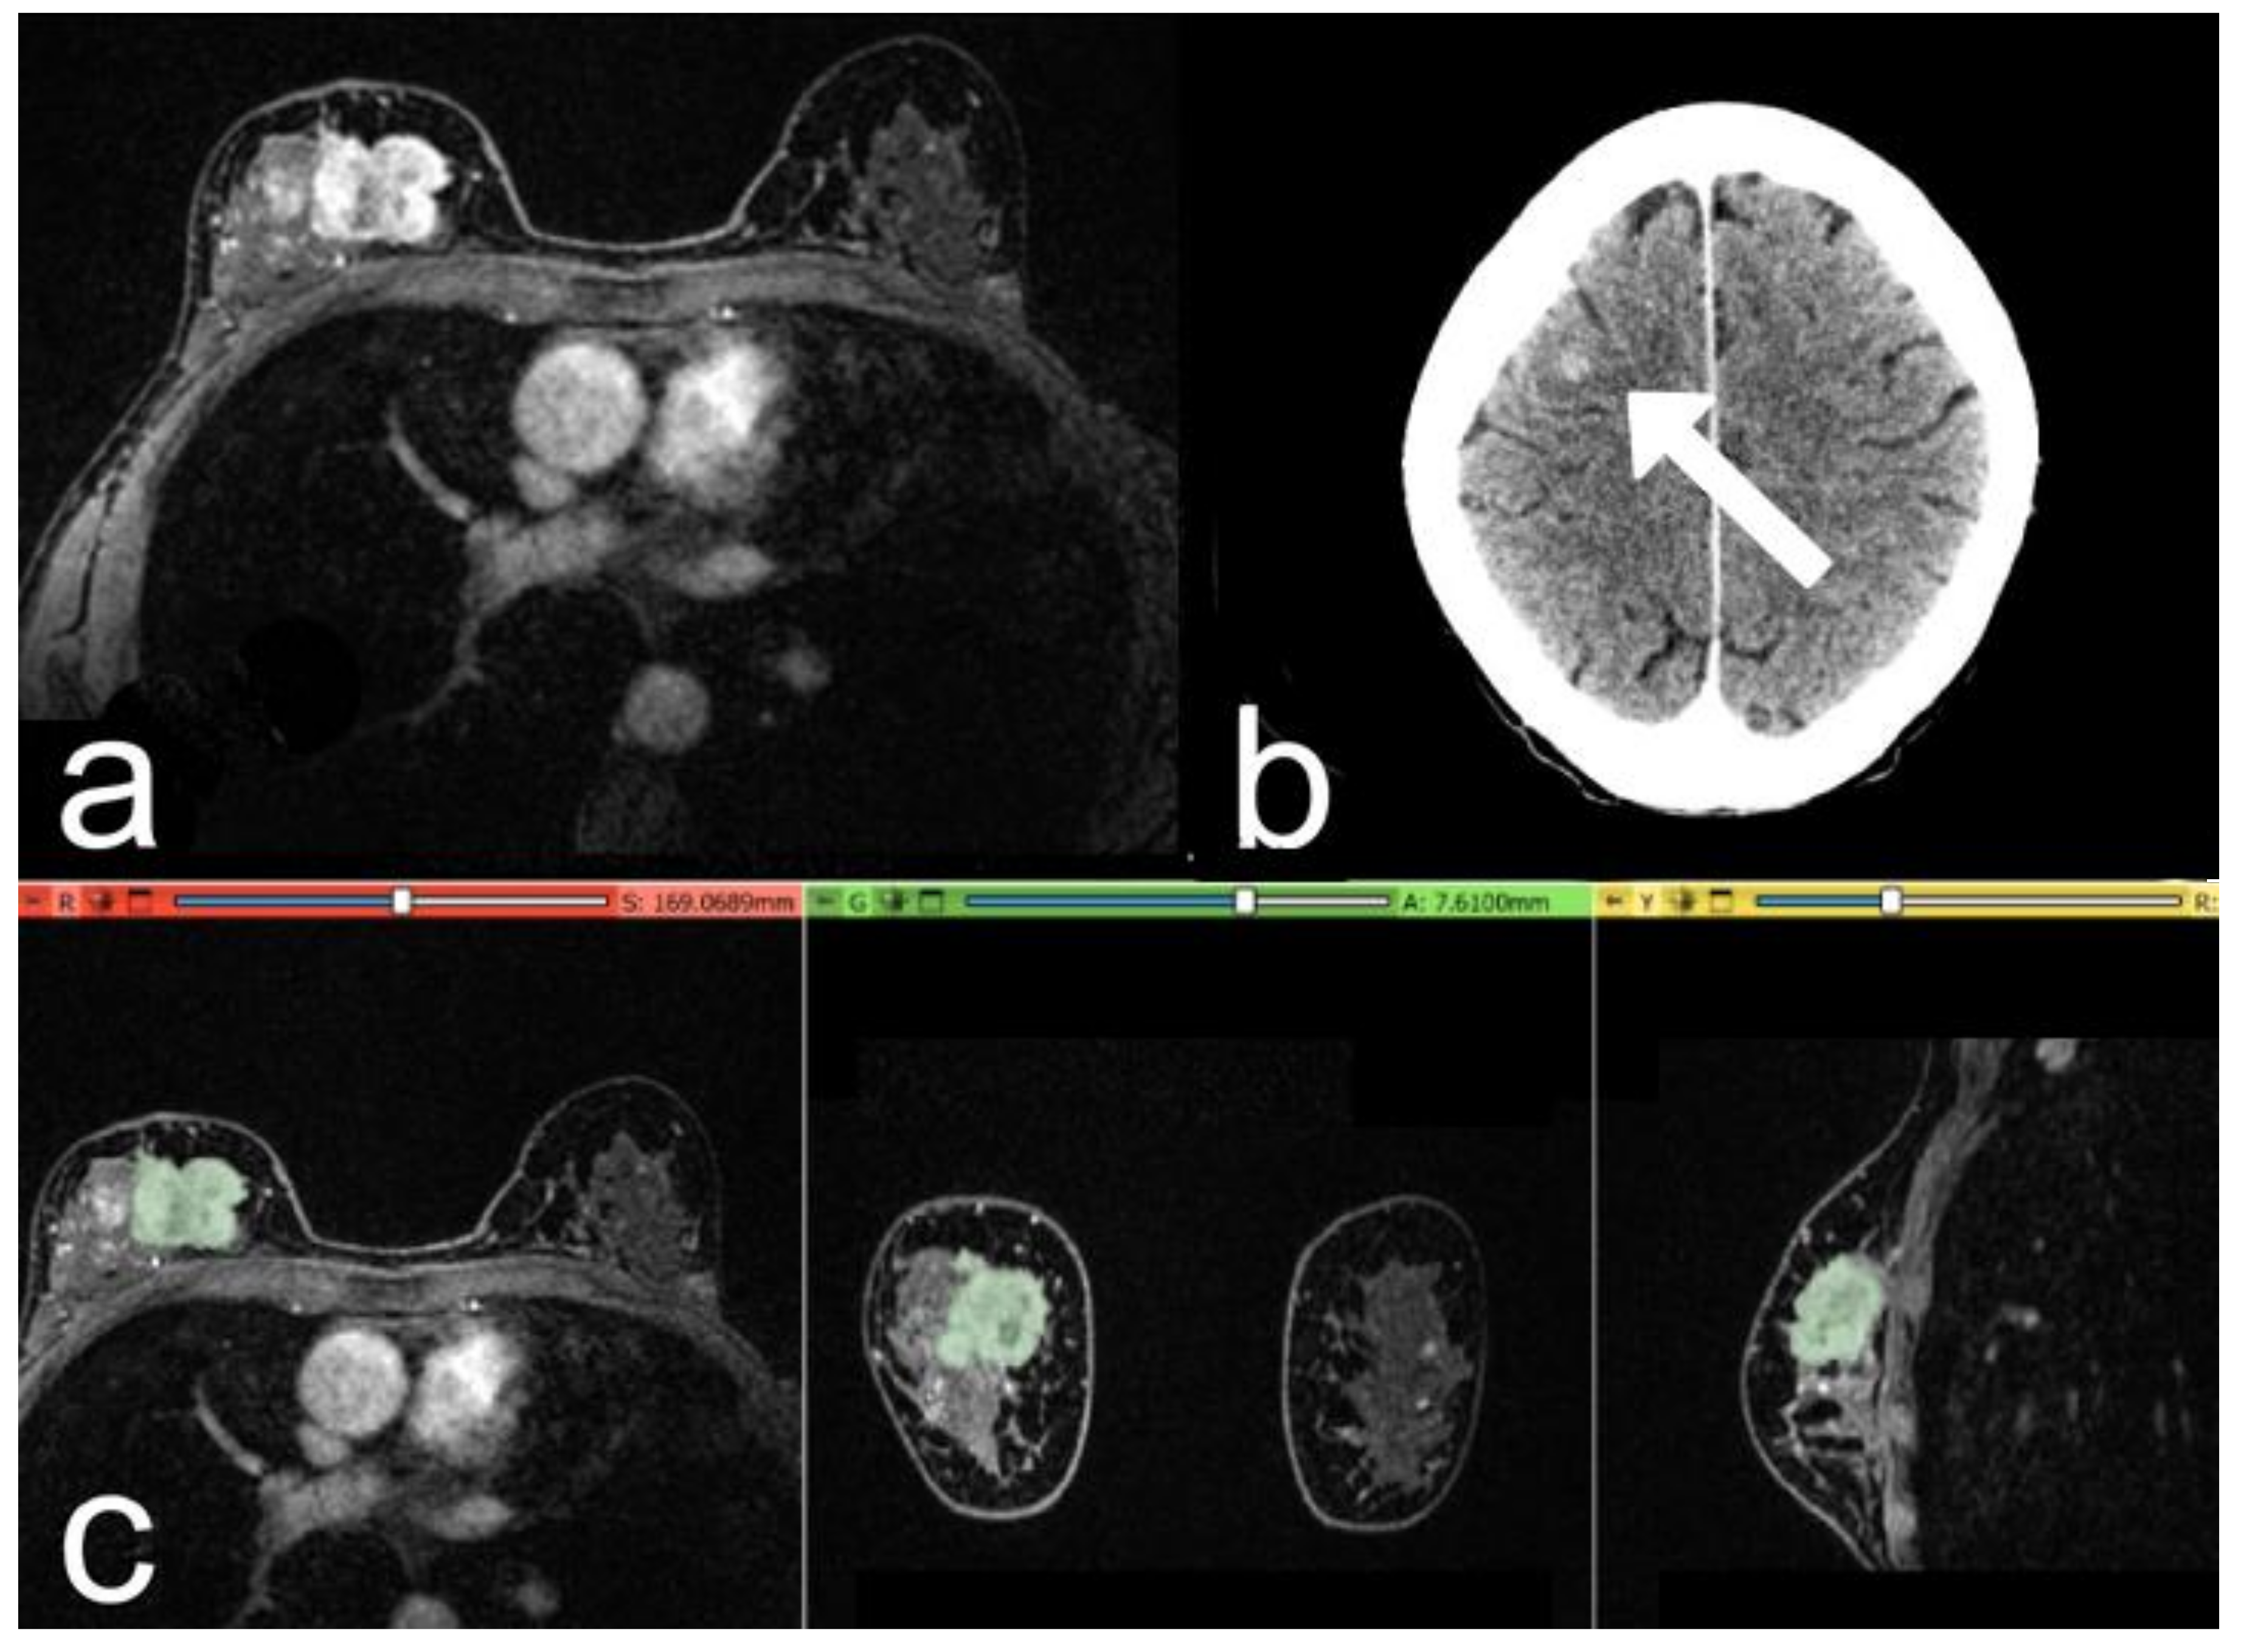

Figure 4.

Case of a 53-year-old woman with a G2 Luminal B invasive ductal carcinoma, Ki-67 of 25%. (a) The post-contrast image shows an irregular mass-enhancing lesion in the upper quadrants of the right breast. (b) At 3-year follow-up: post-contrast axial CT image, with a metastatic nodule in the right frontal lobe (arrow). (c) Representation of the extraction of the segmentation mask.